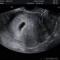

이번에 시험관1차에 바로성공되서

8주차 뿌까맘입니당

오늘은남편이랑 뿌까보러갓는데 너무기여운거잇죠